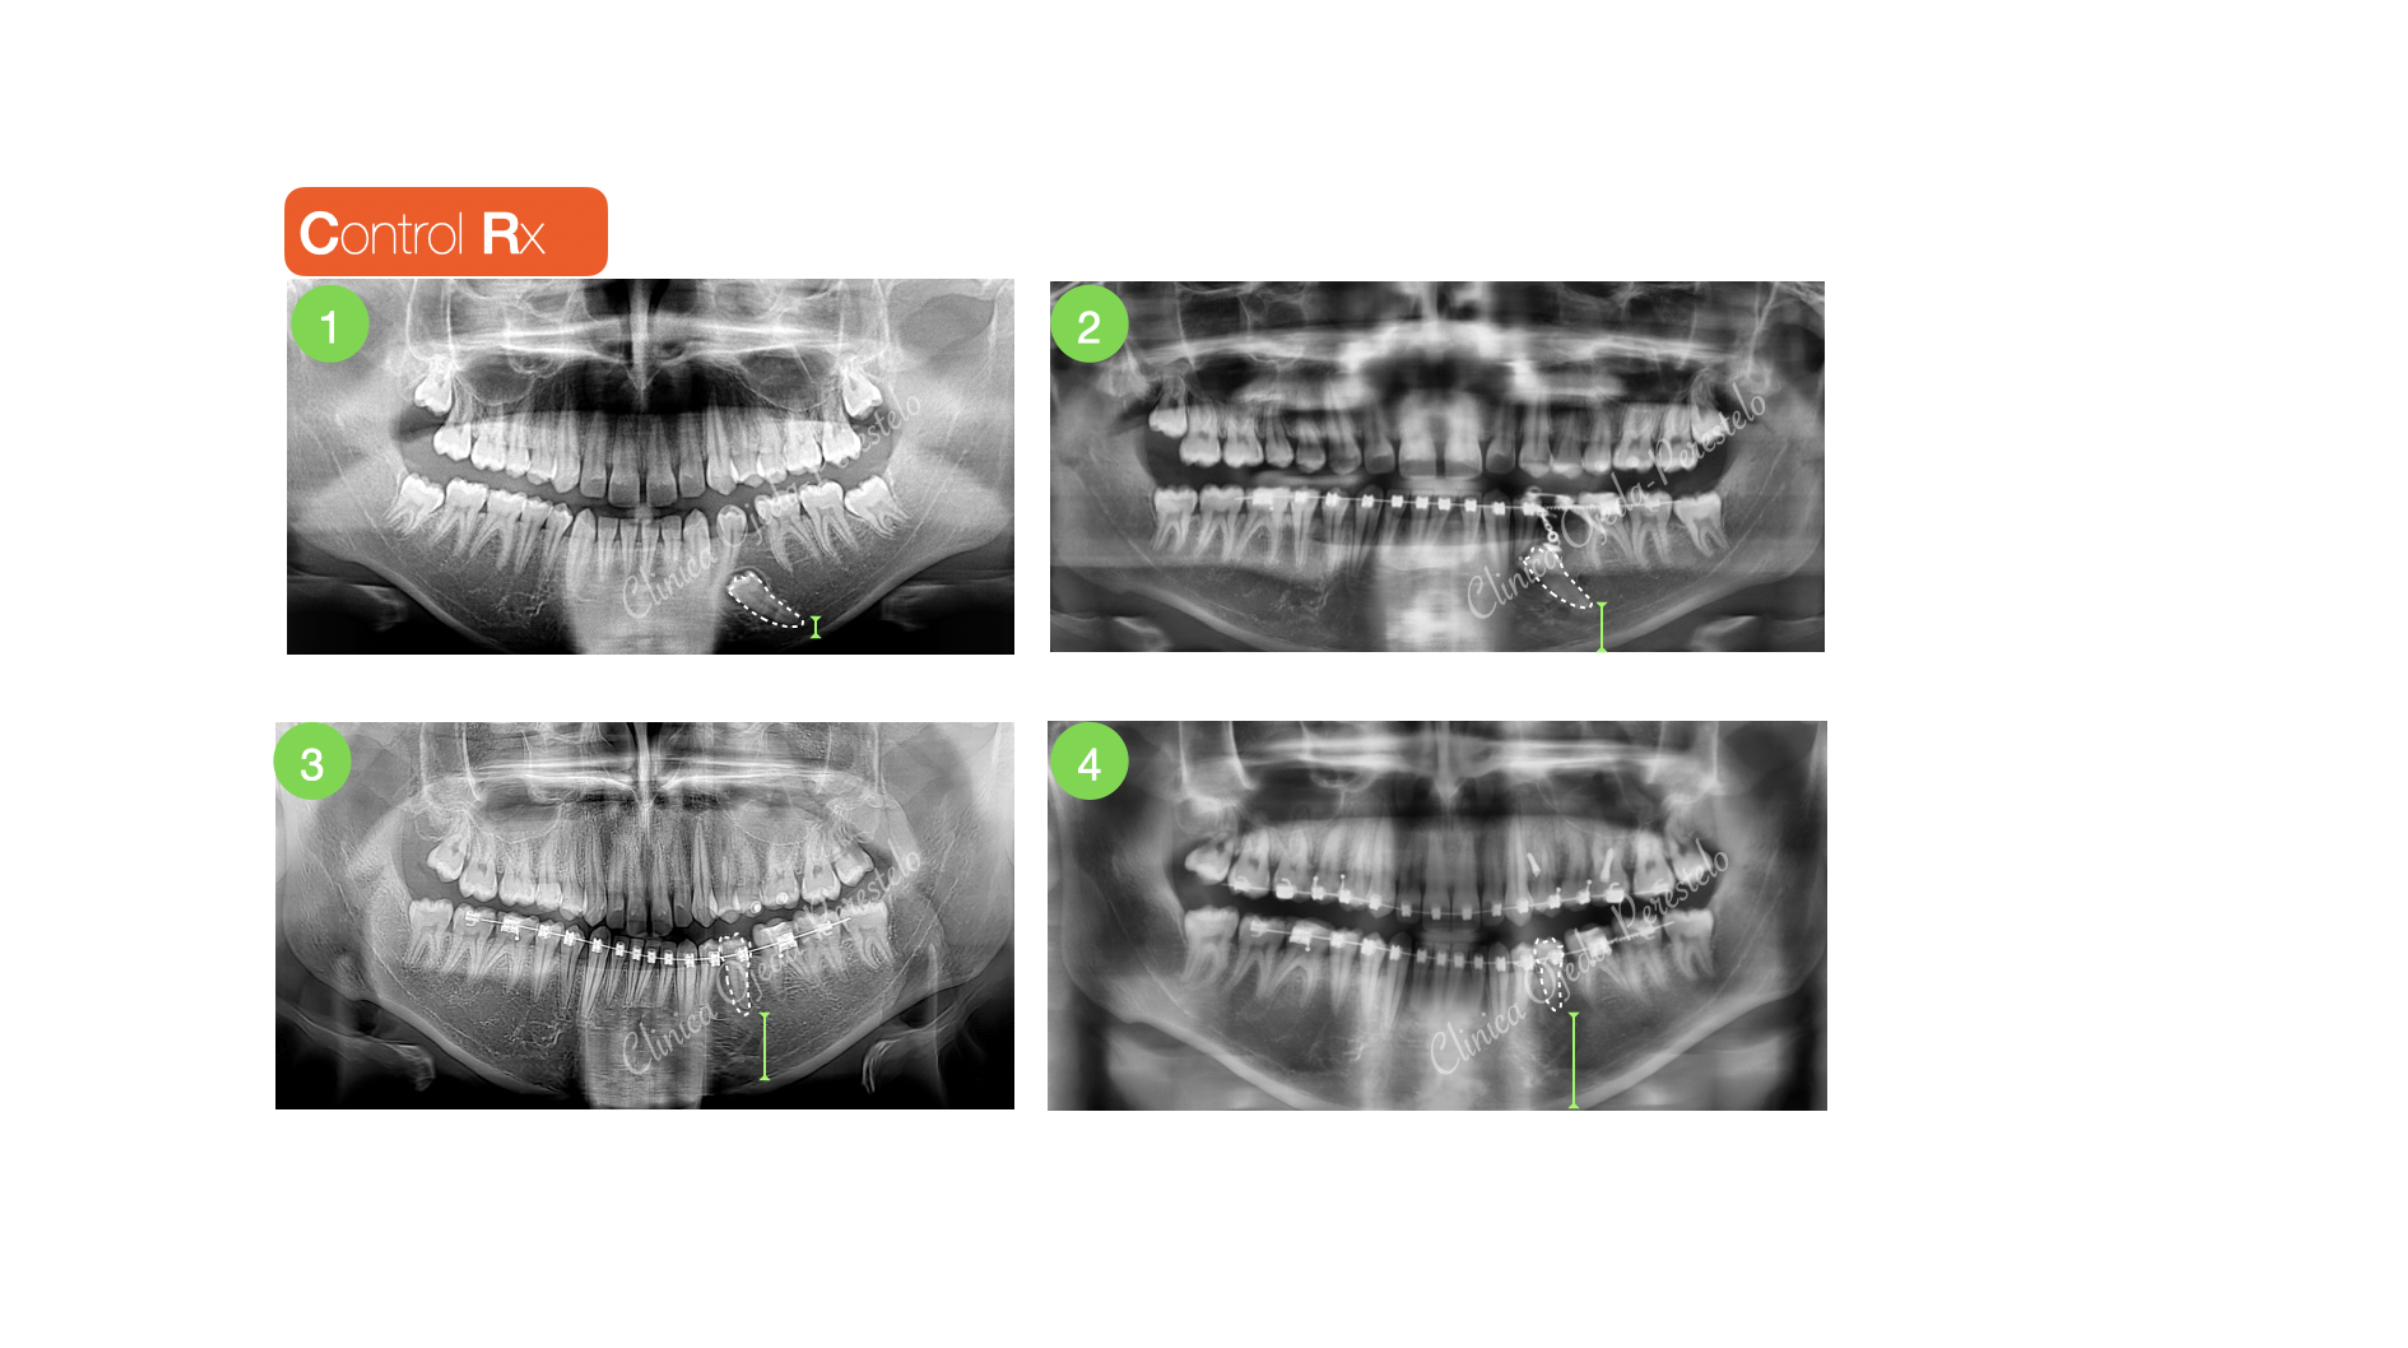

Presentamos a un paciente adolescente con el segundo premolar mandibular (35) retenido y sin posibilidad alguna de erupcionar de manera natural.

Su estudio detallado nos confirma  que se encuentran próximo al borde mandibular y por la cara vestibular. Decidimos fenestrarlo e implementar una combinación de vectores extrusivo-distal y lingual hasta su correcta reubicación dentro de la arcada utilizando como anclaje 1MT con un resorte fabricado a medida. Este protocolo nos permite proteger de posibles reabsorciones radiculares a los dientes de apoyo.

Una vez que el premolar apareció en la arcada terminamos de alinearlo-nivelarlo con brackets ayudándonos de elásticos y 2MT colocados en la arcada antagonista.

Hoy en día los TADs nos han facilitado y simplificado mucho la reubicación de los dientes retenidos y nos han permitido desarrollar estrategias biomecánicas con un mínimo sufrimiento en los dientes adyacentes/apoyo en relación a los procedimientos tradicionales.